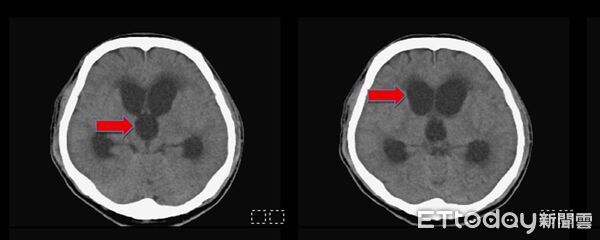

▲手術前腦部斷層掃描,發現所有的腦室脹大(紅色箭頭,黑色部份構造)。(圖/記者許宥孺翻攝)